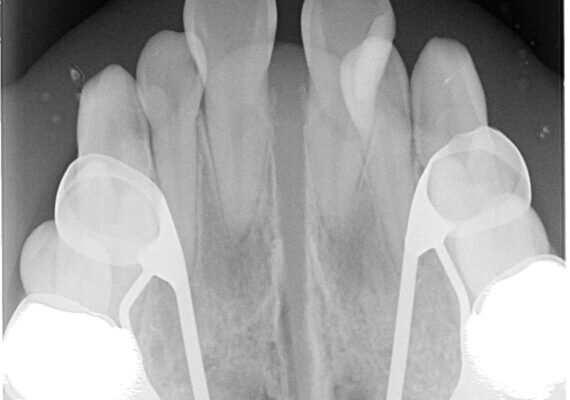

初診時の状態

・上下ともに歯がきれいに並びきらず、がたつきが見られました。

・上下の前歯の中心(正中)がずれています。

・特に上顎の幅が狭いため、下顎の歯列も内側に入り込み、歯が並ぶスペースが不足していました。

• 1年でここまで変わる!歯列のがたつきと正中のズレを改善した矯正治療(メタルブラケット×MARPE) 治療前画像